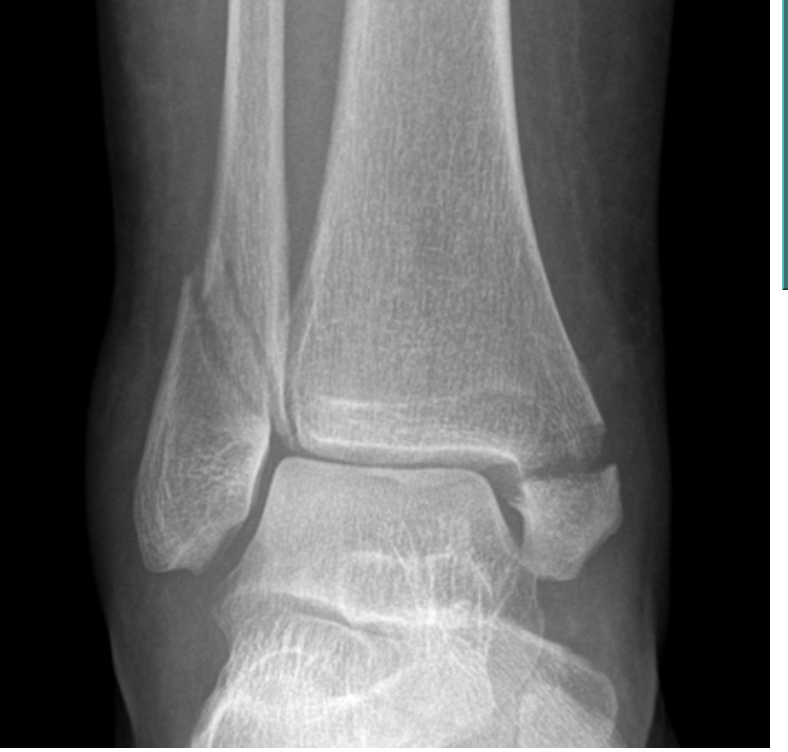

Radiographs demonstrating a disruption of the distal tibiofibular syndesmosis along with a fracture of the proximal fibula, consistent with a Maisonneuve fracture.

Name for this fracture? [1]

Pilon fracture

- These fractures involve the distal tibia and its articular surface.